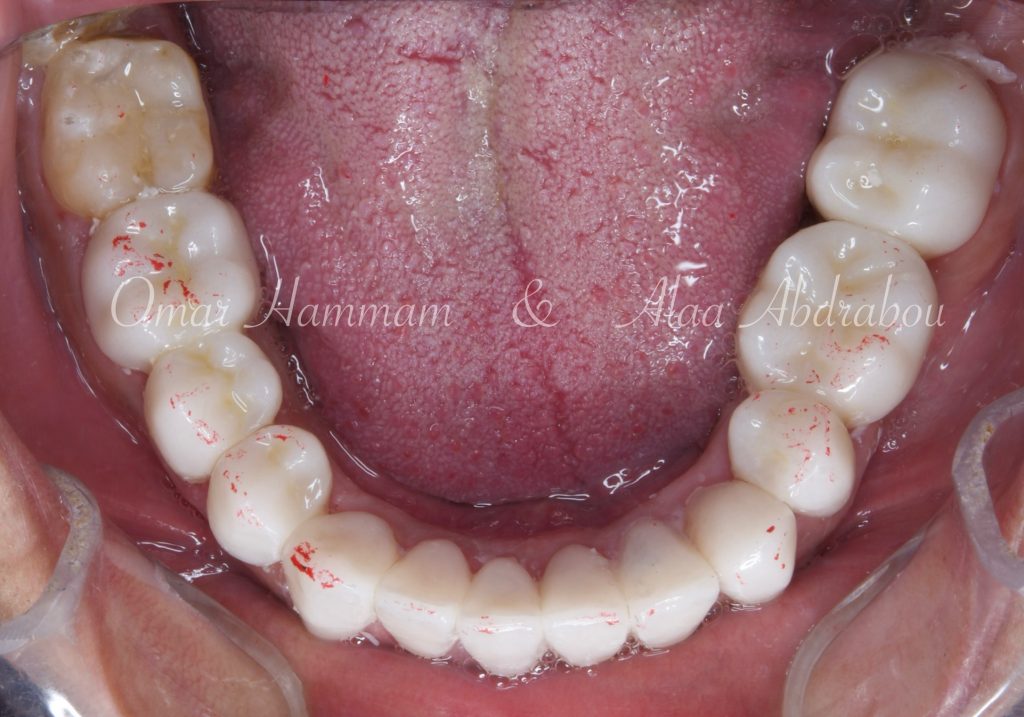

Immediate occlusal scheme after cementation (before any adjustments):

Showing “Occlusal equilibration”, where Stable occlusion is achieved , in which there are Stable contacts of equal intensities on all teeth in centric occlusion showing Group Function occlusion.

Occlusal forces are distributed on more occlusal contacts, Acting as a group to distribute occlusal forces, thereby increasing efficiency of mastication and performing lateral movements atraumatically.